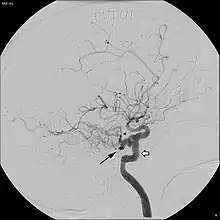

In around 0.1 to 0.6% of individuals, as sampled by magnetic resonance angiography, the trigeminal artery fails to involute and remains in the adult brain, in a condition called persistent trigeminal artery.[3] This condition is more common in women than in men, with approximately 1.8 times as many women having the condition.[6] Knowledge of a persistent trigeminal artery may be important in certain brain surgeries, as the condition is rare and an accidental cut to the artery could lead to hemorrhage.[1] Although the discovery of a persistent trigeminal artery is sometimes an incidental finding, its presence is also associated with various pathological conditions, and must therefore be considered carefully when diagnosing these conditions.[7]

A persistent trigeminal artery is associated with an increased risk of aneurysm, though some studies have suggested that this finding may be an effect of selection bias, as most individuals do not undergo the tests necessary to identify the condition.[3] Persistent trigeminal artery has been identified as a rare cause of trigeminal neuralgia, with 2.2% prevalence of persistent trigeminal artery among trigeminal neuralgia patients.[8] Surgery to move the persistent trigeminal artery away from the trigeminal nerve has been successful in treating the trigeminal neuralgia in some cases.[9] In some cases, presence of a persistent trigeminal artery concurs with hypoplasia of the basilar artery, in which case the internal carotid artery is responsible for most blood flow to the upper pons, cerebellum, midbrain, and parts of the temporal and occipital lobes, meaning that anything disrupting blood flow in the internal carotid artery could lead to ischemia in these regions.[10] In addition, persistent trigeminal artery has been associated with vertebrobasilar insufficiency, brainstem ischemia, and carotid cavernous fistulae.[2]